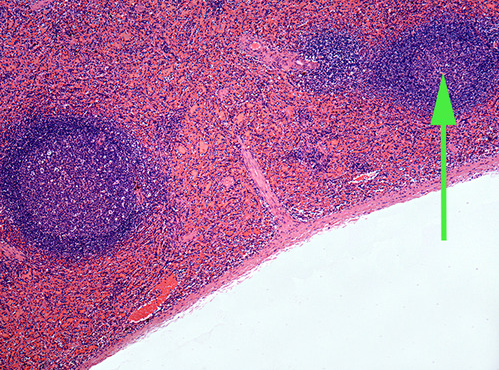

The diffuse lymphatic tissue found in the structure marked by the green arrow is called peyer's PATCH

The green arrow is indicating the peyer's patch in this area of the small intestine. It is made up of a dense accumulation of what kind of cells?//lymphocytes

diffuse lymphatic tissue called peyer's patches in the wall of the intestinal tract.